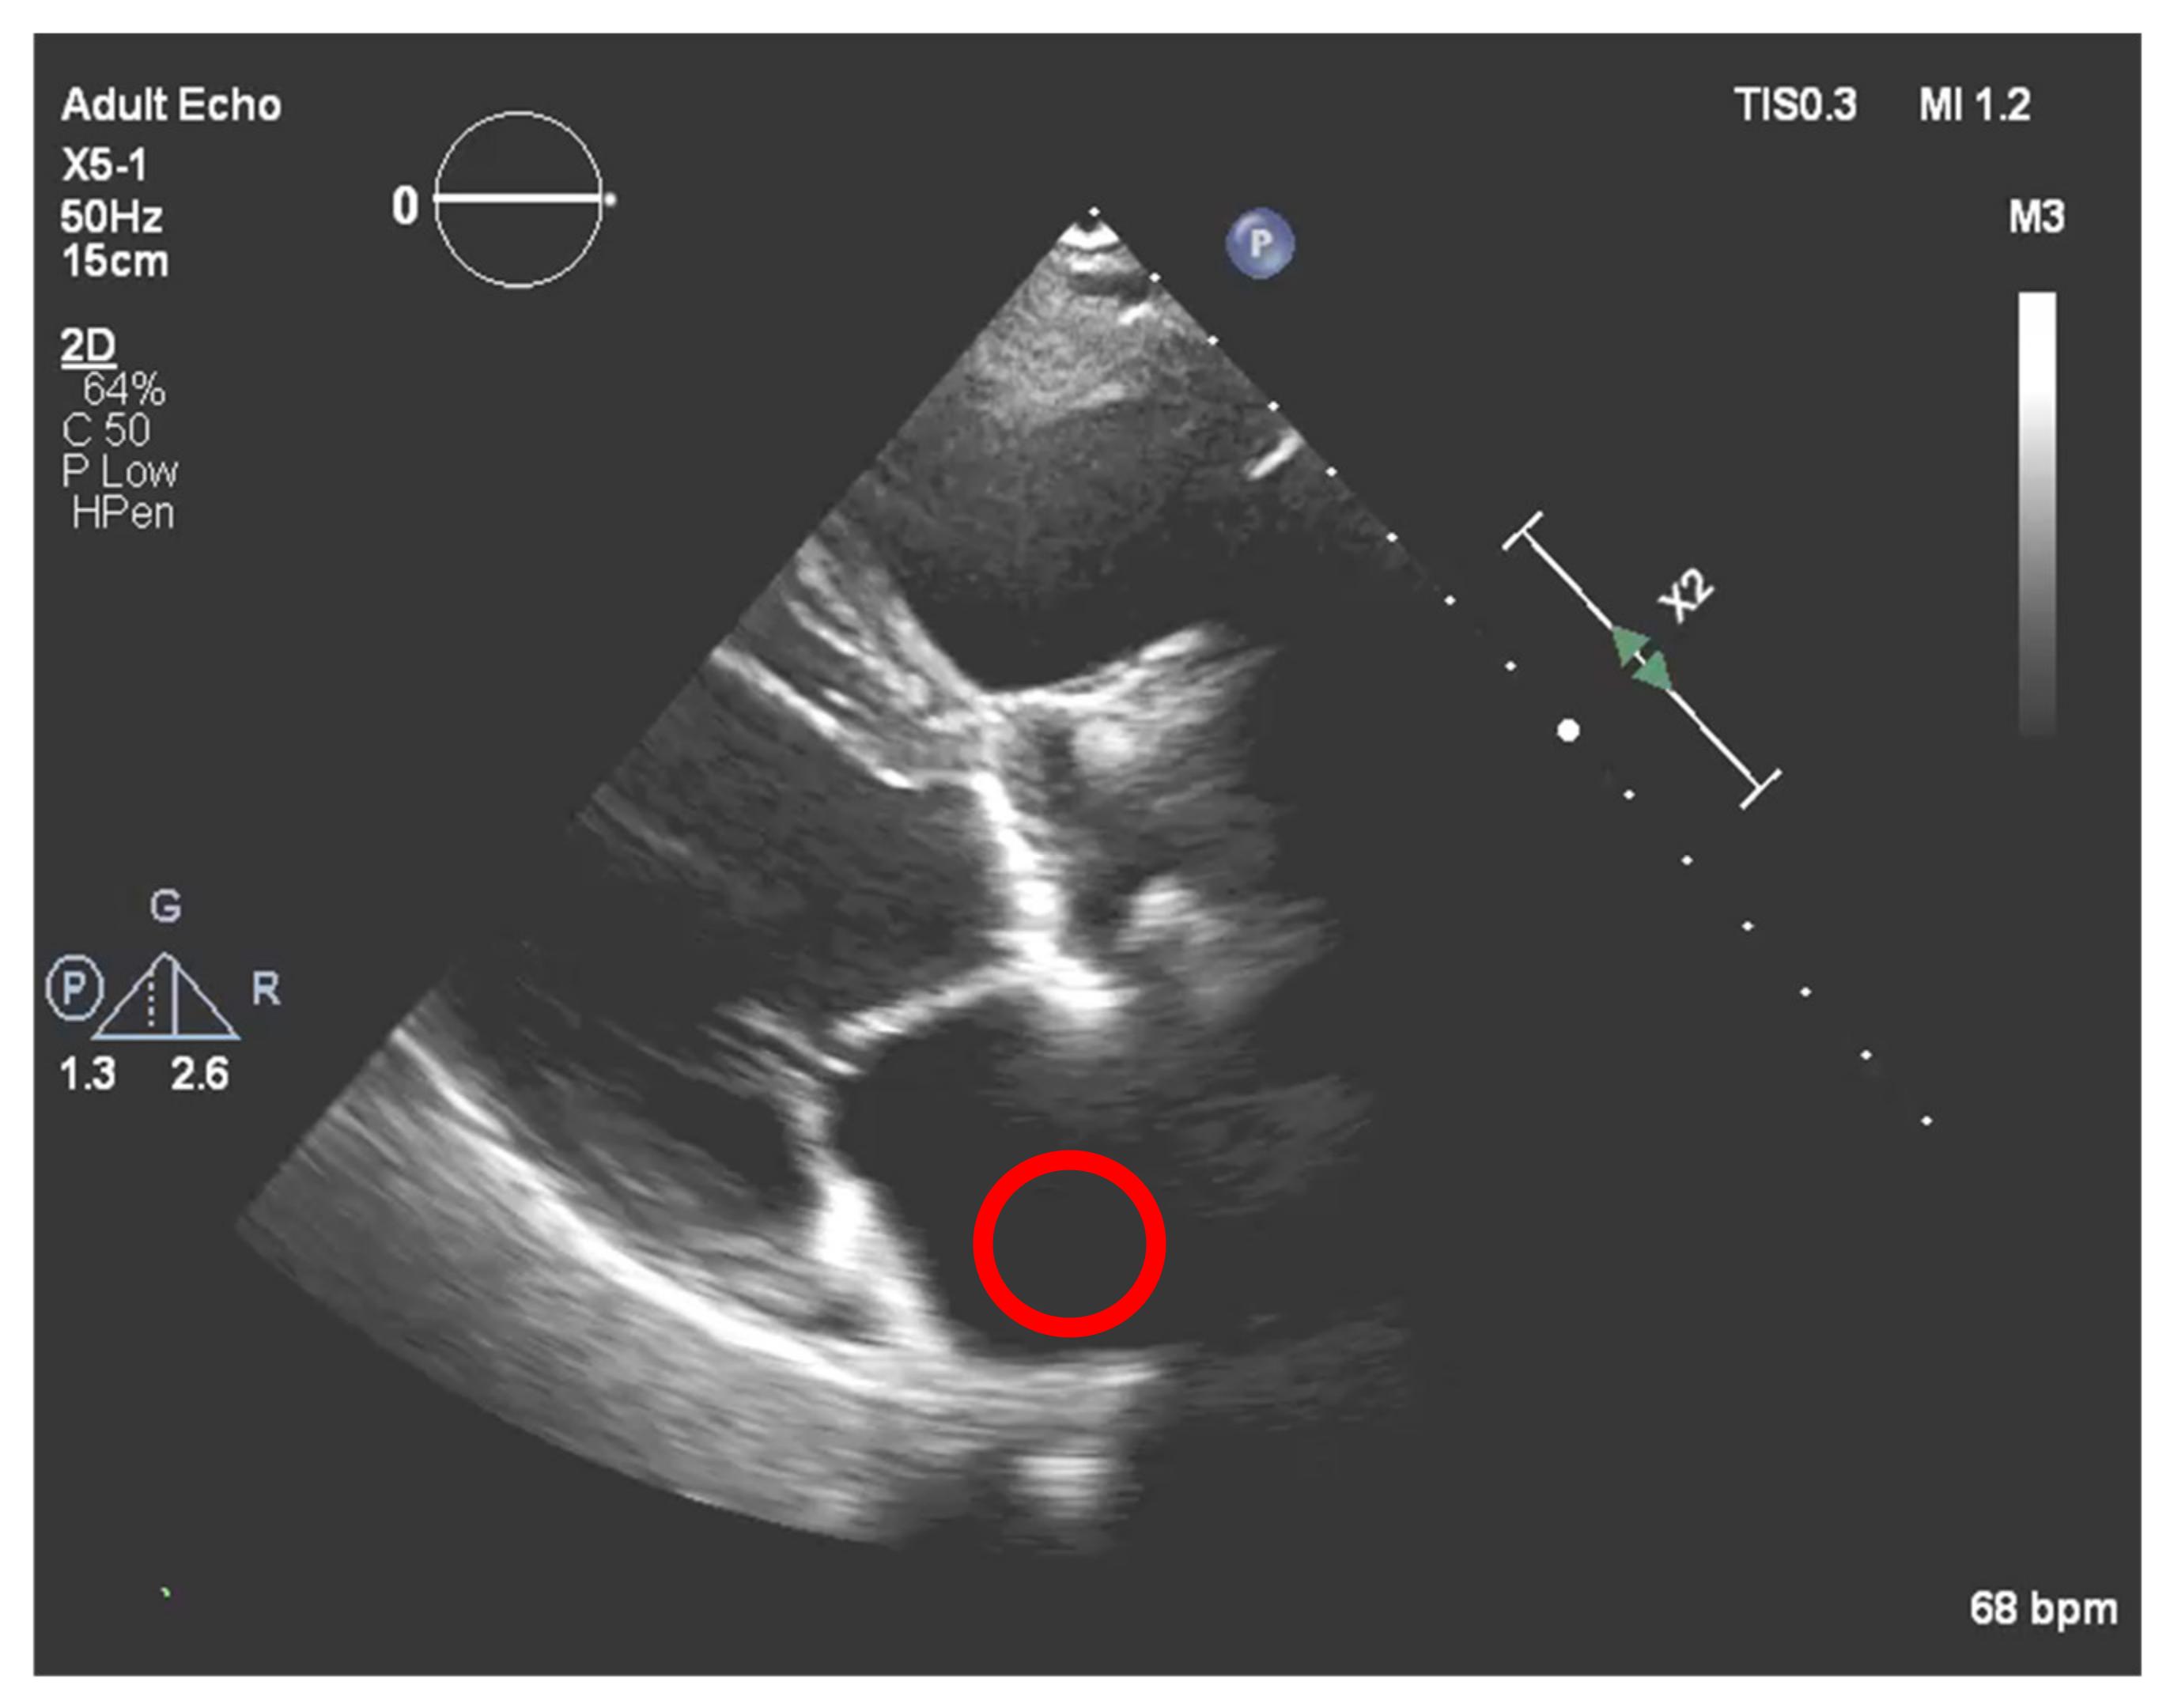

This method was tested on several images. Figure 8 depicts the example of one echocardiography with the most used different types of gains set in a post-processing stage, with the settings Window Width fixed at 250 and Window Level (WL) permuting between 75, 100 and 125.

Figure 8. Echocardiography examples with different Windrow Levels (WL) and fixed Window Width of 250 (1) WL = 75, (2) WL = 100, and finally, (3) WL = 125.